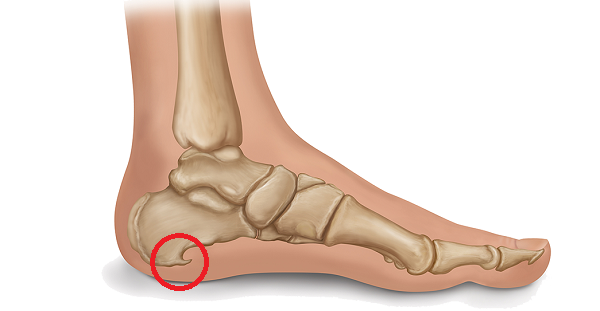

Sabe aquele esporão que insiste em aparecer no seu calcanhar? Pois é, ele é uma calcificação que surge no osso, bem na parte de baixo do calcâneo (o osso do seu calcanhar). Pensa nele como um pequeno “bico” de osso que se forma. Ele aparece justamente ali porque é um ponto de muita pressão e tensão na nossa pisada. A faixa de tecido que liga o calcanhar aos dedos, a fáscia plantar, sofre um estresse constante, e o corpo, na tentativa de proteger, cria essa estrutura óssea.

O mais importante é entender que nem sempre o esporão causa dor. A dor que você sente é, na verdade, uma inflamação na fáscia plantar. O esporão é só uma consequência. Mas quando a dor aparece, ela costuma ser mais forte pela manhã, ao dar os primeiros passos, ou depois de ficar um tempo sentada e levantar. O alívio nem sempre é imediato, mas com os cuidados certos, dá pra controlar e viver sem esse incômodo. Vamos cuidar desse calcanhar!